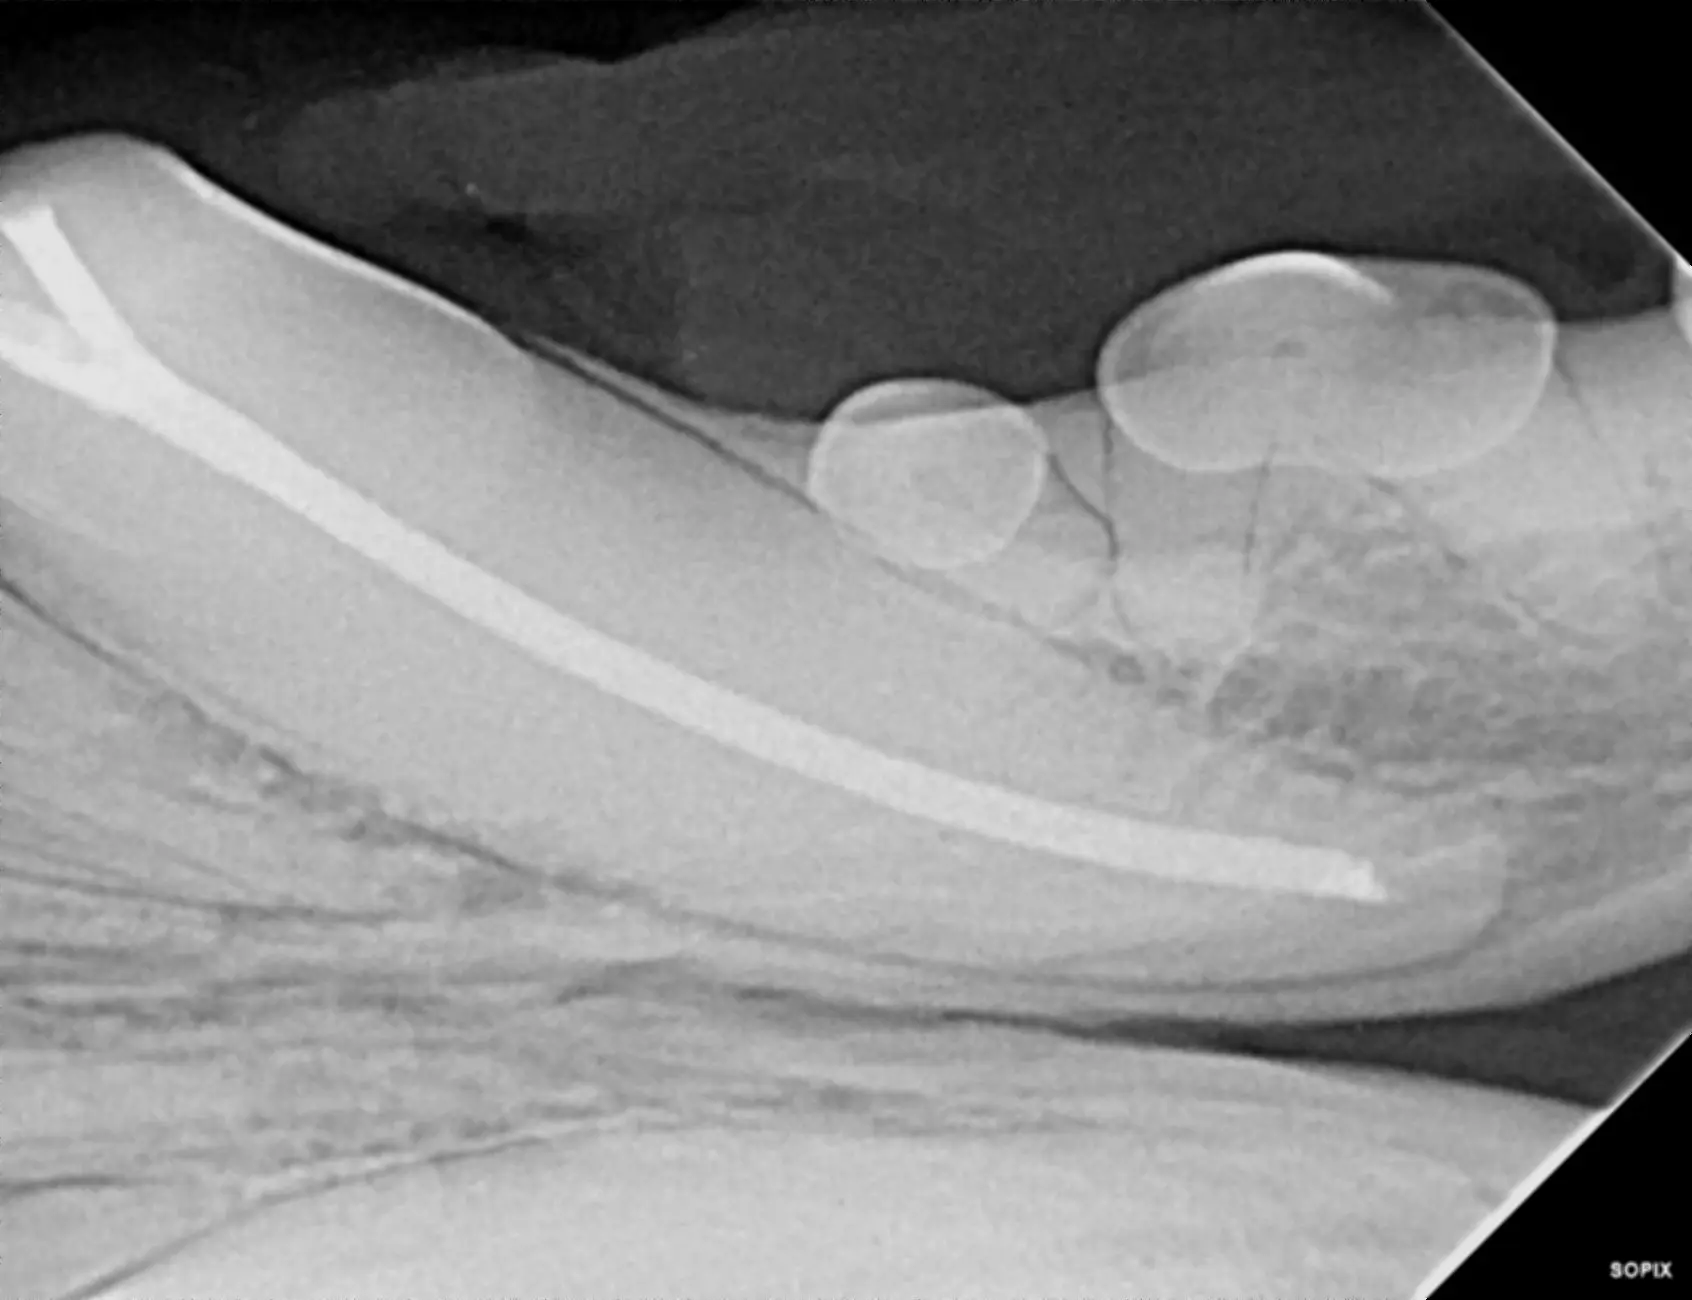

Endodontics refers to the treatment of the inside of the tooth. Indications include fractured teeth with pulp exposure, non-vital teeth, and teeth that have to be shortened due to malocclusion. Endodontic procedures are used as an alternative to extraction, allowing the tooth to be maintained in the mouth. Not every tooth is a good candidate for endodontic treatment, so we use diagnostic imaging to help us make that determination.

Root canal treatment is an endodontic procedure performed on fractured and non-vital teeth in adult animals. The procedure entails removing diseased pulp from the canal, which is then carefully cleaned, disinfected, filled, and sealed. Usually, root canal treatment can be performed from start to finish in one visit, but on some occasions, it may require staged treatment to be successful. If root canal treatment cannot be fully completed in a single visit, the canal will be filled with a temporary filling material, and a second procedure will be needed to complete the process.